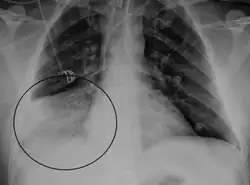

HMPV may cause mild upper respiratory tract infection (e.g., the common cold). However, premature infants,[15] immunocompromised persons,[16][17][18][19] and older adults >65 years [14][20][21] are at risk for severe disease and hospitalization. In some studies of hospitalizations and emergency room visits, HMPV is nearly as common and severe as influenza in older adults.[14][20][21][22] HMPV is associated with more severe disease in people with asthma[23][24][25][26] and adults with chronic obstructive pulmonary disease (COPD).[27][28][29] Numerous outbreaks of HMPV have been reported in long-term care facilities for children and adults, causing fatalities.[30][31][32][33][34]